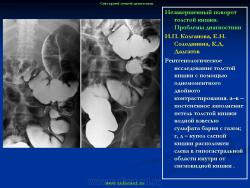

Варианты и аномалии развития толстой кишки.